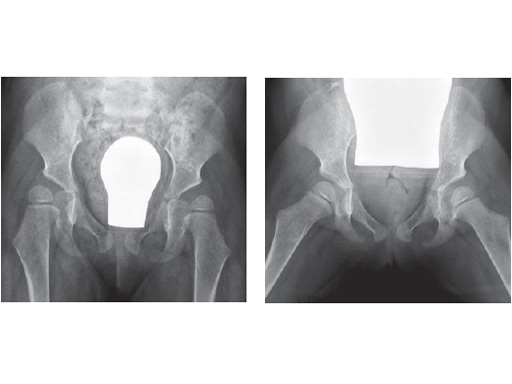

4-years-old female, CP, good walker

Fig. 1

Hip instability due to severe hip dysplasia and severe coxa valga

Fig. 2

Abduction shows an acceptable containment; a 35 varus OT bilateral in combination of a triple OT on the right is planned

Fig. 1-2